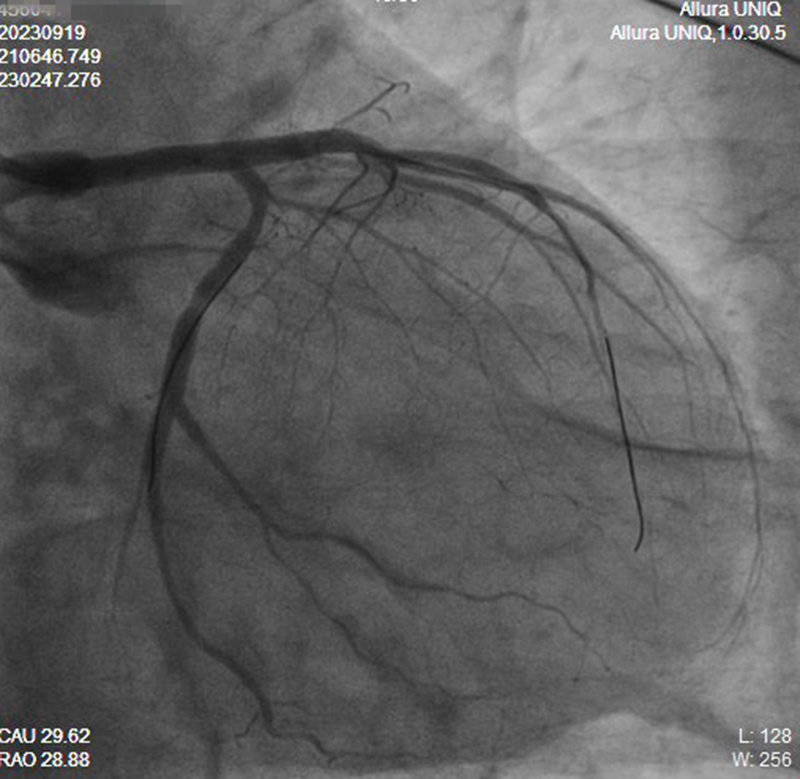

生机稍纵即逝,吴大叔随时可能猝死!面临最凶险的心梗,救心团队沉着应对,先使用球囊扩张血管梗塞部位,再接入主动脉球囊反博(IABP),稳定血压,纠正心源性休克,最后连续植入两枚心脏支架,成功恢复全部血流。

【支架植入后左主干造影,血供恢复】

整个救心过程一气呵成,入导管室至导丝通过时间为17分钟,DtoW 52分钟。手术一开通血管,吴大叔就明显感觉不适症状缓解,心衰、心源性休克也得以控制。